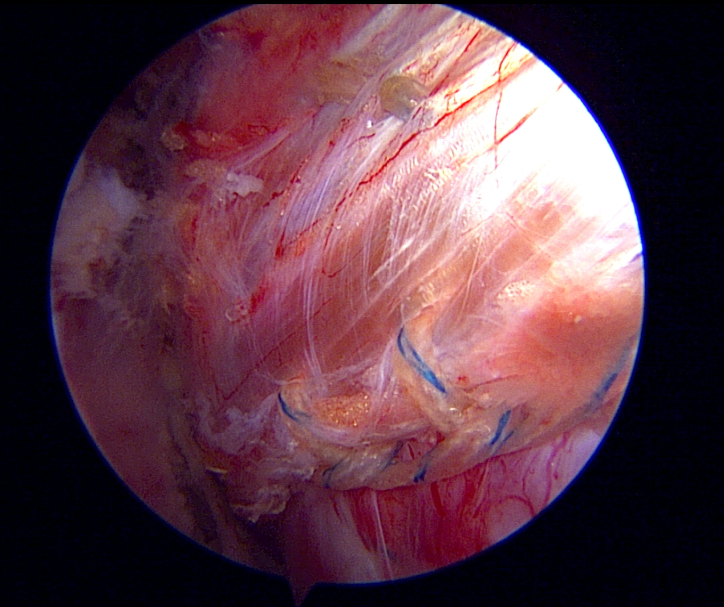

Artroskopi Yardımlı Latissimus Dorsi Tendon Transferi (LDTT)

Masif onarılamaz rotator manşet yırtıklarında (MIRCT) uygulanan latissimus dorsi tendon transferi tekniği. Sırt kasının tendonu omuz bölgesine transfer edilerek kaybedilen omuz fonksiyonu yeniden kazandırılmaktadır.

Artroskopik görüntü — masif manşet retraksiyonu